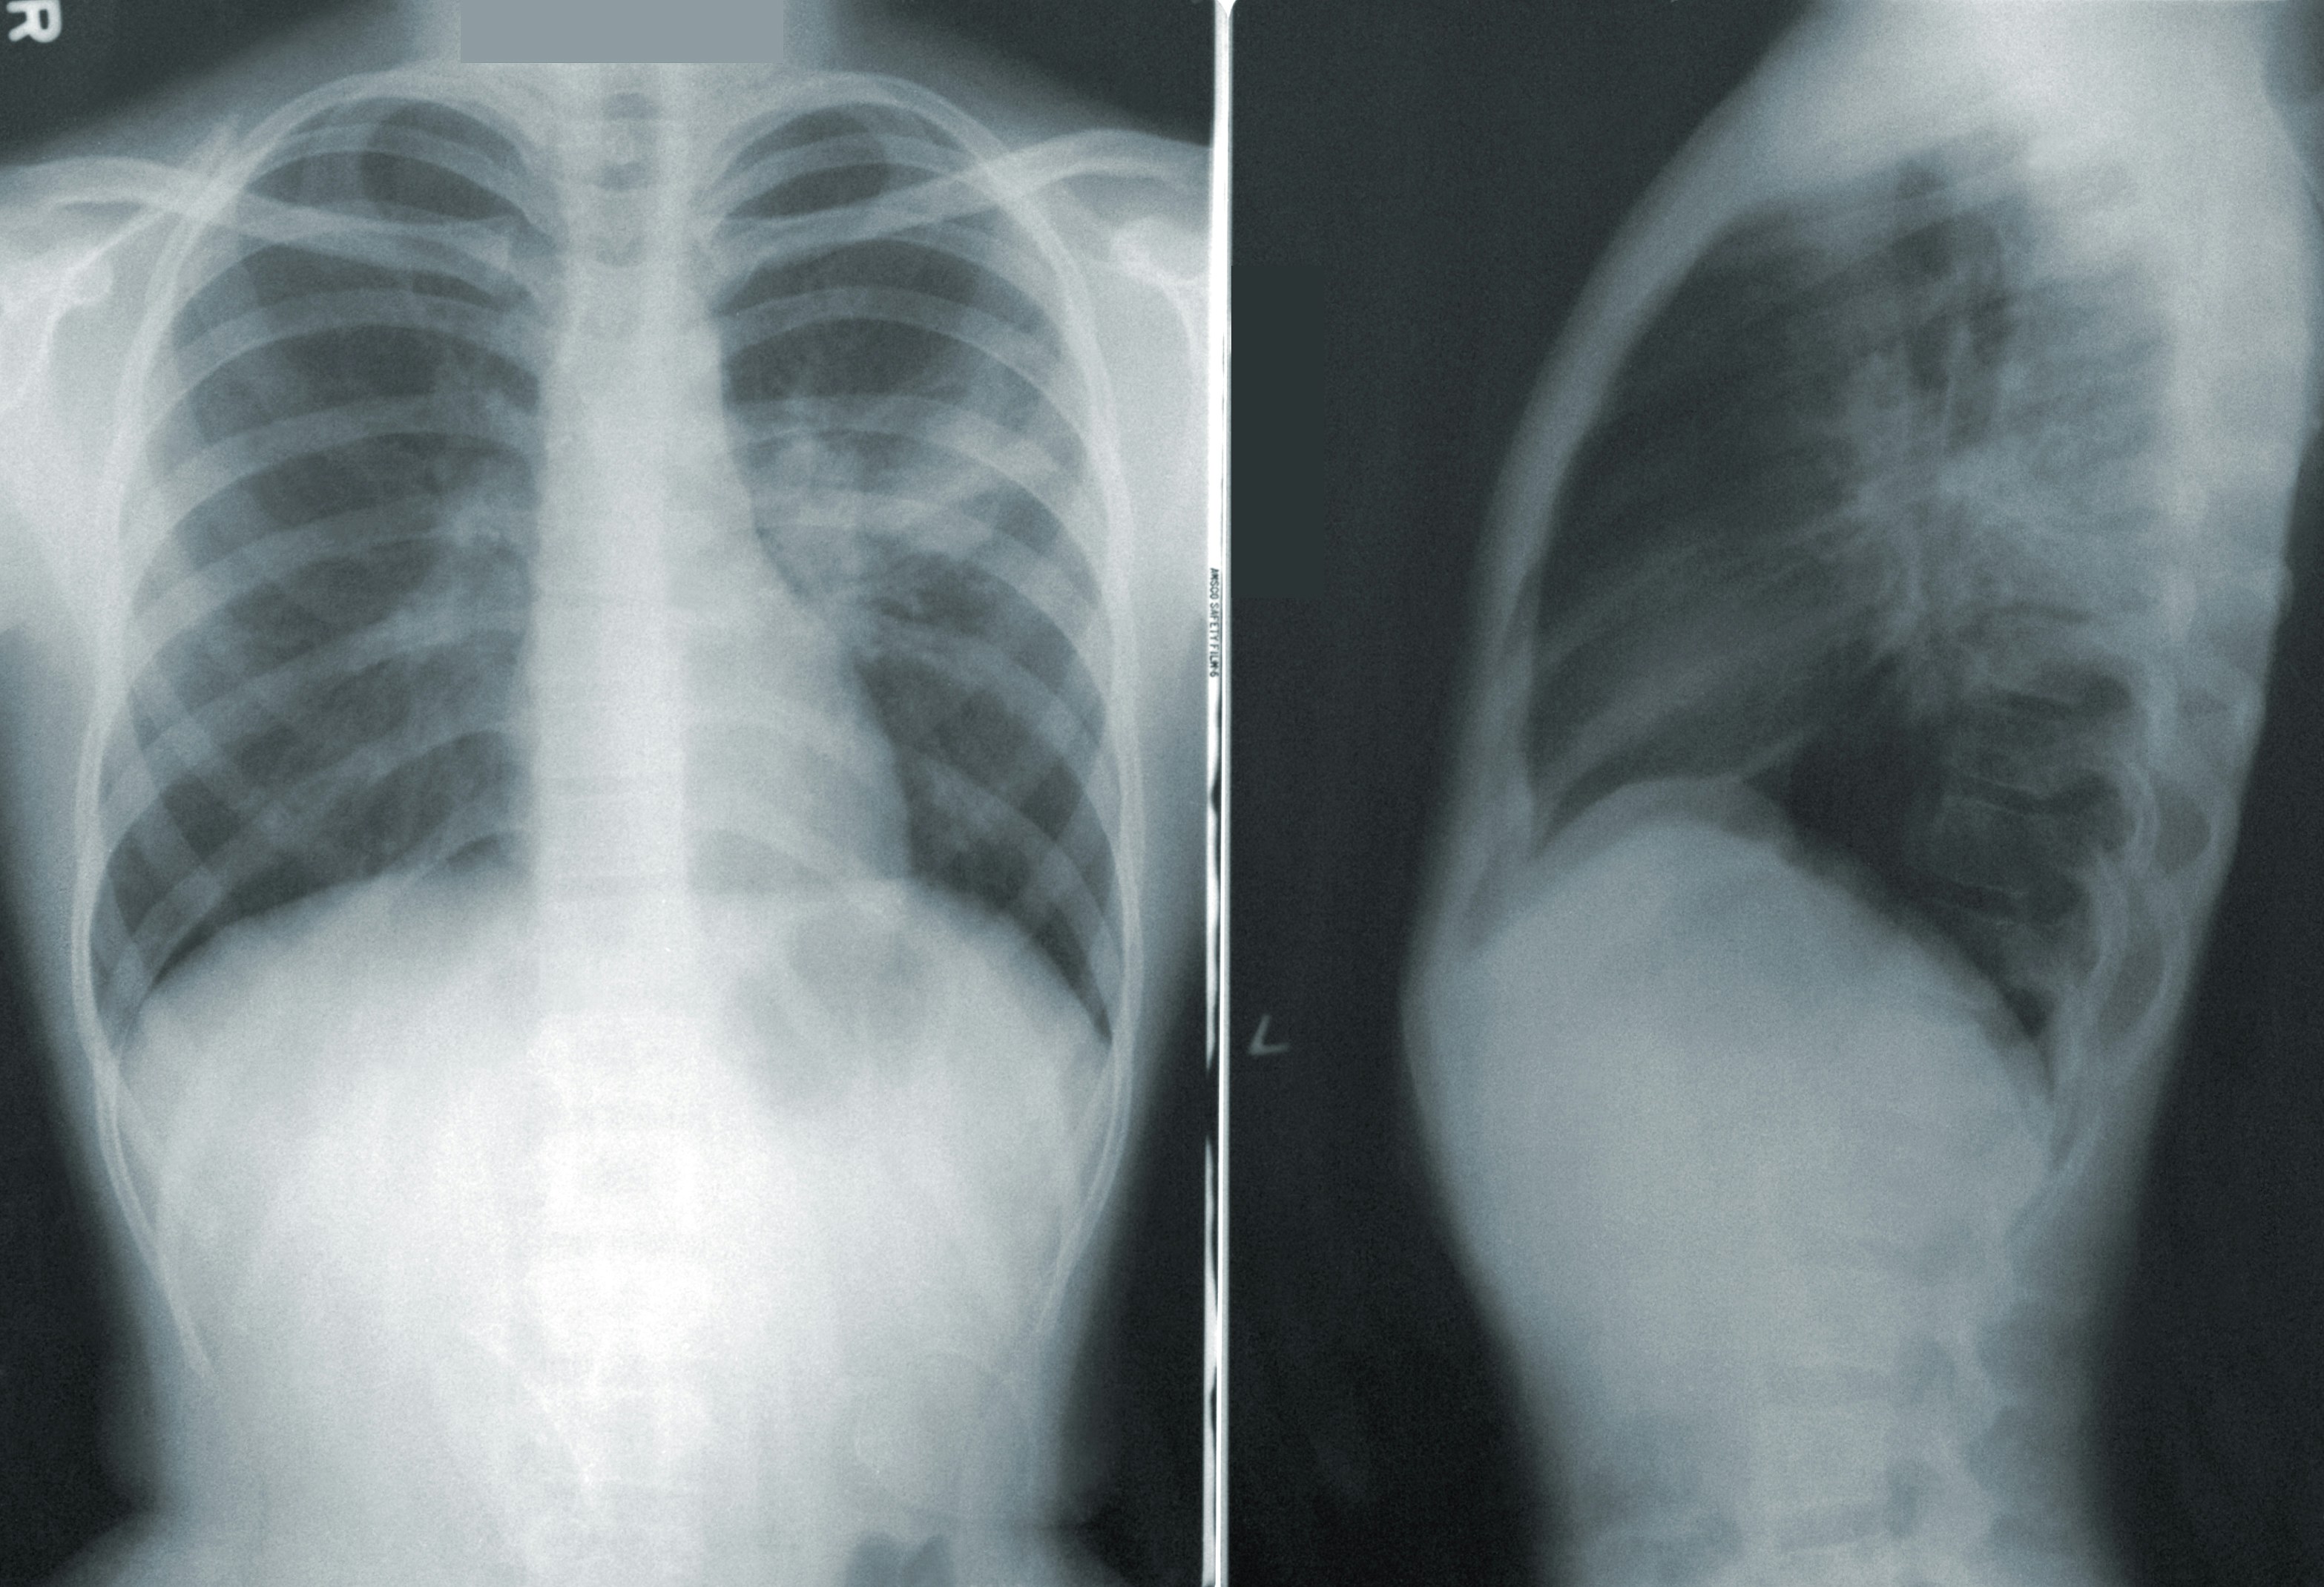

Nakon što je napravljen rendgen, otkriven je "oštar metalni predmet", a liječnici su shvatili da je riječ o nožu, okruženom "gnojem i nekrotičnim tkivom". Nož je u tijelo ušao kroz desno rame.